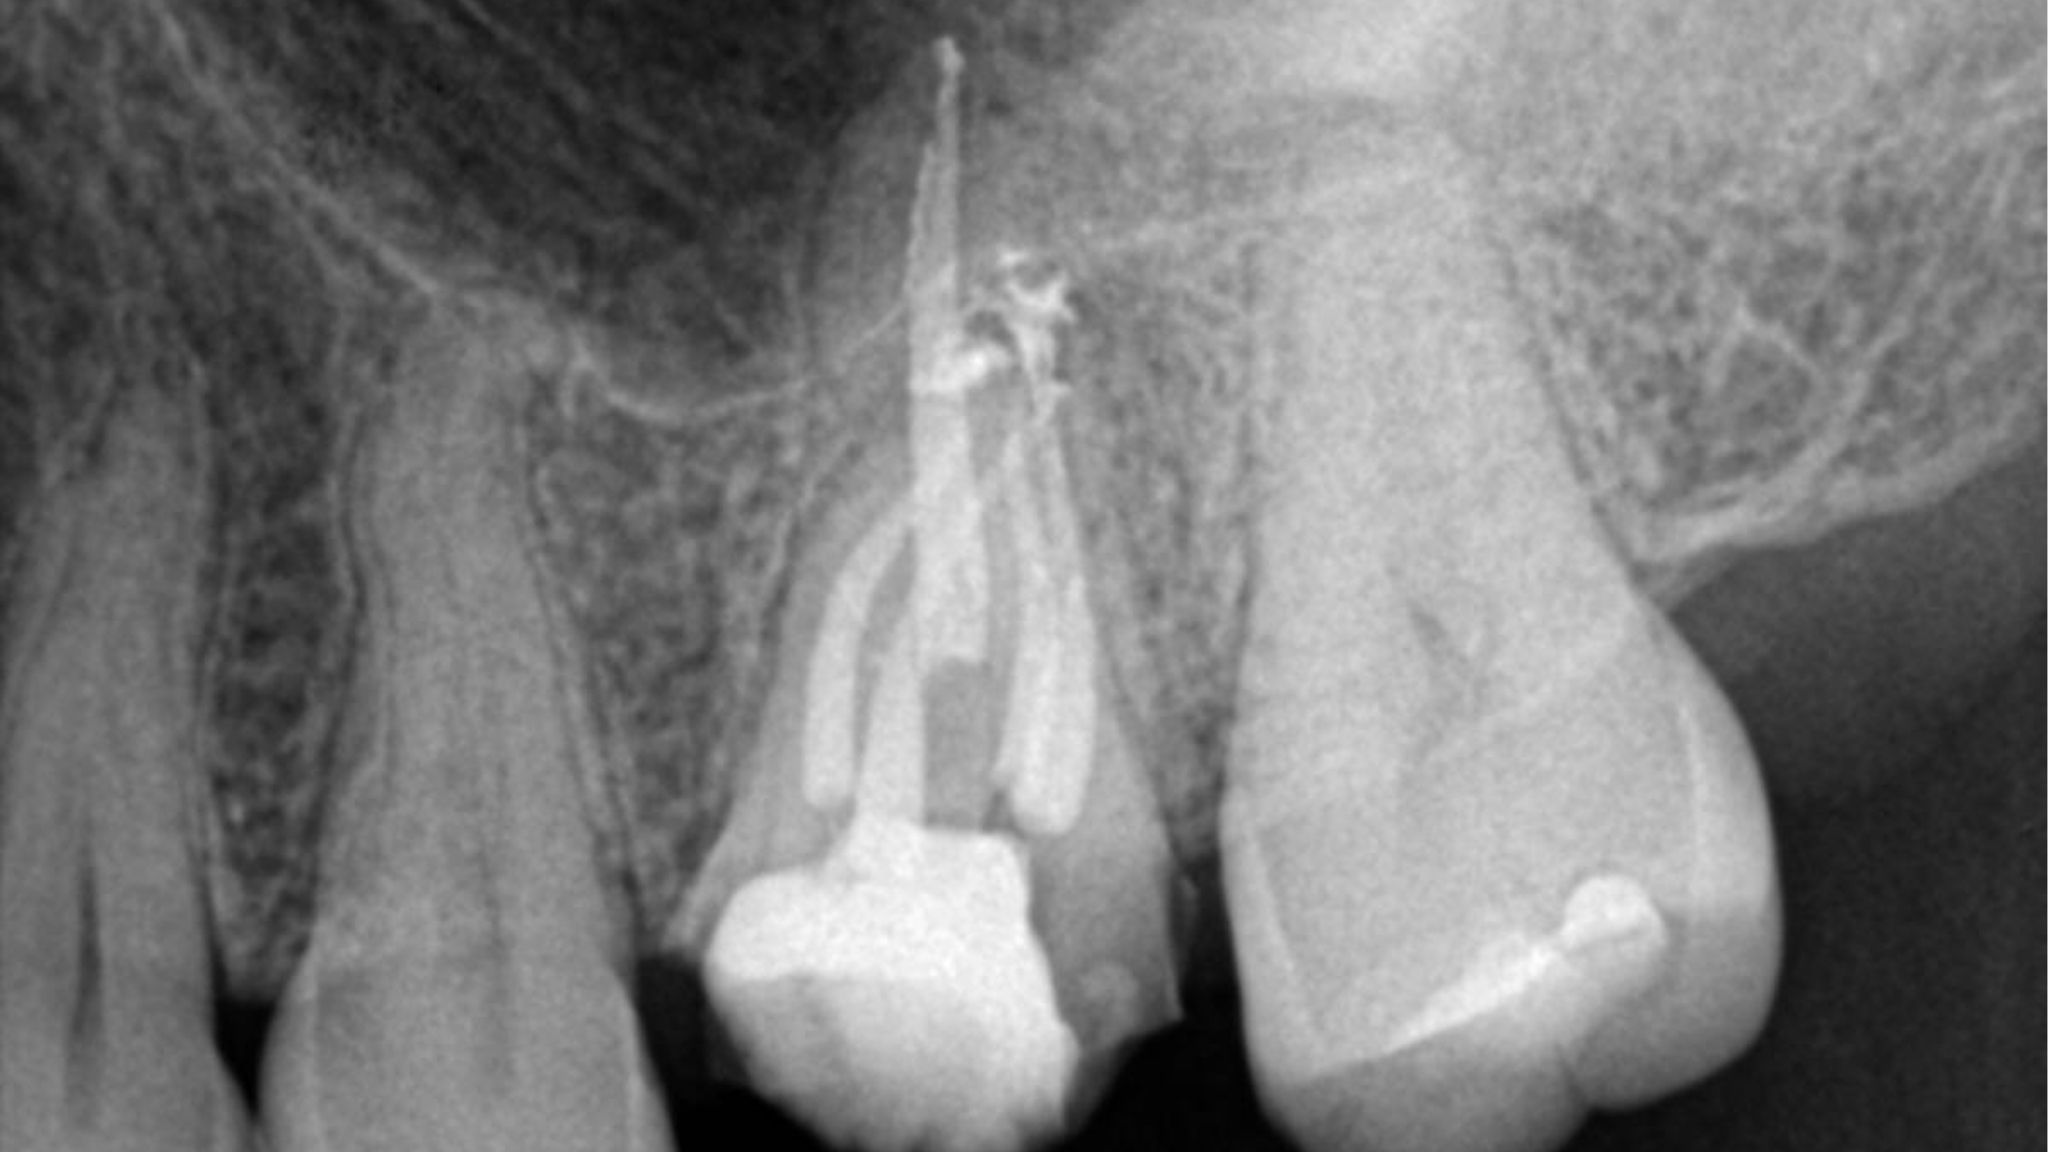

The Lateral Puff in Endodontics: Clinically Significant or a Storyteller of Anatomy and Etiology? – A Case Report Series

In modern endodontic practice, the focus has shifted from traditional cleaning, shaping, and filling methods to prioritizing conservative canal shaping first, opening the canals, and using advanced disinfection protocols with irrigation, enabling more effective cleaning before three-dimensional filling.1 To be more accurate and descriptive of root canal anatomy, it is recommended to use the term … Read more